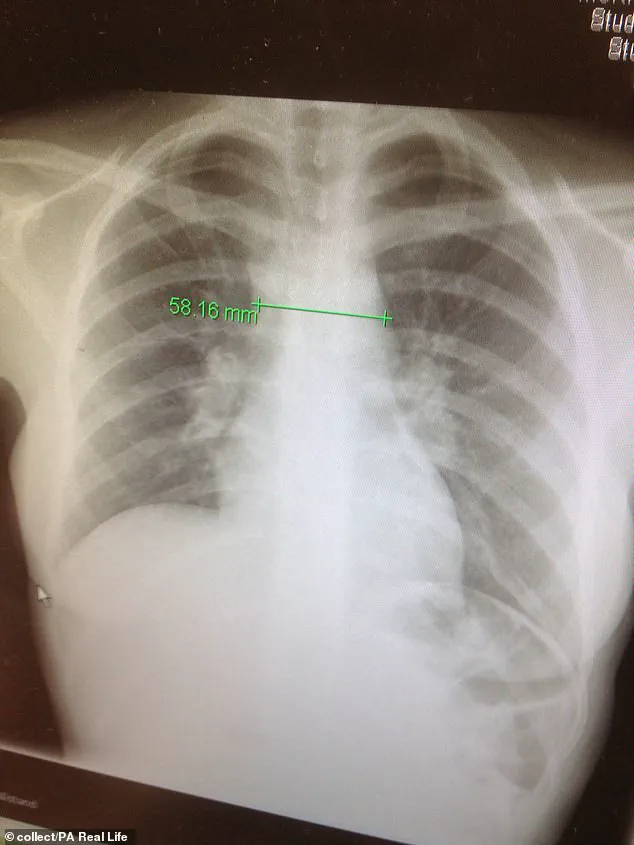

One of the most significant concerns for Katherine was the increased risk of breast cancer due to the substantial radiation therapy administered in her chest region during her initial battle with Hodgkin lymphoma.

Given the extensive chest and abdominal radiation she had received earlier, concerns about long-term health impacts loomed large.

In particular, the risk of developing breast cancer became a significant worry.